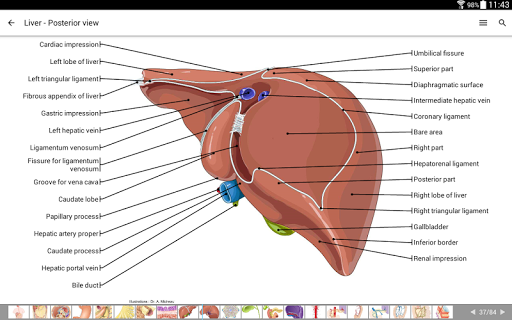

IMAIOS e-Anatomy es un atlas de anatomía humana para médicos, radiólogos, estudiantes de medicina y técnicos en radiología. Echa un vistazo a más de 26 000 imágenes médicas y anatómicas de forma gratuita antes de suscribirte a nuestro detallado atlas de anatomía humana.

e-Anatomy se basa en el galardonado atlas en línea IMAIOS e-Anatomy. Lleva contigo la referencia más completa de anatomía humana, dondequiera que vayas, en tu dispositivo móvil o tableta.

e-Anatomy tiene más de 26 000 imágenes que contienen series de imágenes en vistas axiales, coronales y sagitales, así como radiografías, angiografías, imágenes de disección, gráficos anatómicos e ilustraciones. Todas las imágenes médicas fueron etiquetadas cuidadosamente, más de 967 000 etiquetas disponibles en 12 idiomas, incluida la Terminologia Anatomica latina.

- Toque las etiquetas para mostrar las estructuras anatómicas